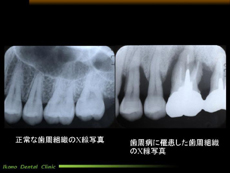

「神経を一度取ればもう痛まない」と誤解なさっているのだと思います。図1

このようなときは「歯が浮いたようになって、痛くて噛めない」状態になります。これは歯の中の神経が痛んでいるわけではなく、歯の周囲の組織が痛んでいるのです。(図1)

目に見えない、地味な治療ですが、きちっと治療すれば神経を取った後のトラブルはずっと少なくなります。(図2)

クリックすると拡大してご覧になれます

歯の根っこが化膿した状態

図1

歯の神経治療のレントゲン写真

図2